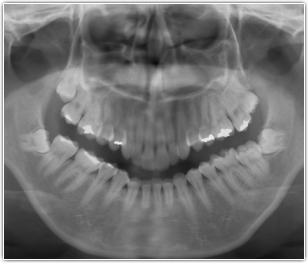

難しい症例も高い技術と経験で抜歯可能です。

はぎわら歯科は抜歯の技術に自信があります。最新の設備・高い技術力・長年の経験から、難しいとされる事例も的確な処置で安全に抜歯を行います。難しいケースはCTにより精査します。大学病院へ紹介される歯科医院も多いと思いますが、大学病院へ行く時間のとれない方は当院にて対応いたします。他の歯科医院の先生からも数多く依頼を受けています。